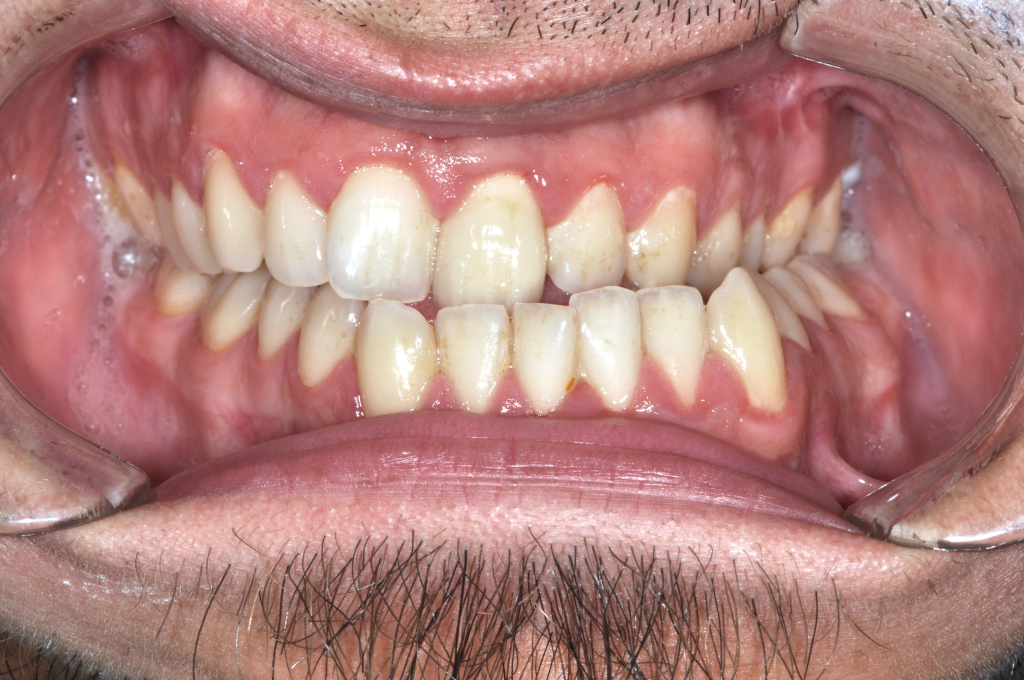

Előtte fogsor - Nyitott harapás kezelése állcsontműtéttel

Utána fogsor - Nyitott harapás kezelése állcsontműtéttel

A kiindulási állapotban elöl nem jött létre fogérintkezés.

A nyitott harapás hátterében állcsonti pozíciós eltérés állt, nem a fogak helyzete.

Fogszabályozással előkészítettük a műtétet, majd állcsonti korrekciót végeztünk.

A felső állcsont helyzetének módosításával zártuk az elülső harapást,

az alsó állkapcsot pedig funkcionálisan stabil pozícióba állítottuk.

Eredmény: zárt, terhelhető harapás, javuló rágófunkció, stabil ízületi helyzet.